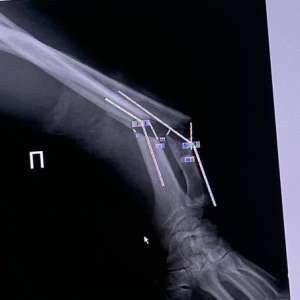

Омич отрезал себе руку циркулярной пилой во время ремонта. Кисть удалось спасти.

По данным СМИ, 50-летний Константин Корнилов распиливал доски во время ремонта у себя дома, в какой-то момент рука соскочила, и пила практически отрезала ему кисть, которая повисла на сухожилии. У пострадавшего были разрезаны кости, вены, артерии.

Его экстренно госпитализировали в районную больницу. Врачи смогли спасти руку. По их словам, операция была непростая: сперва наложили аппарат Илизарова, а уже после сшивали сосуды между спицами и железными кольцами. А также восстановили кровоток — без него кисть была бы обречена.

Спустя две недели пациента выписали — пока его руку фиксирует аппарат. Скоро Константину предстоит ещё одна операция.